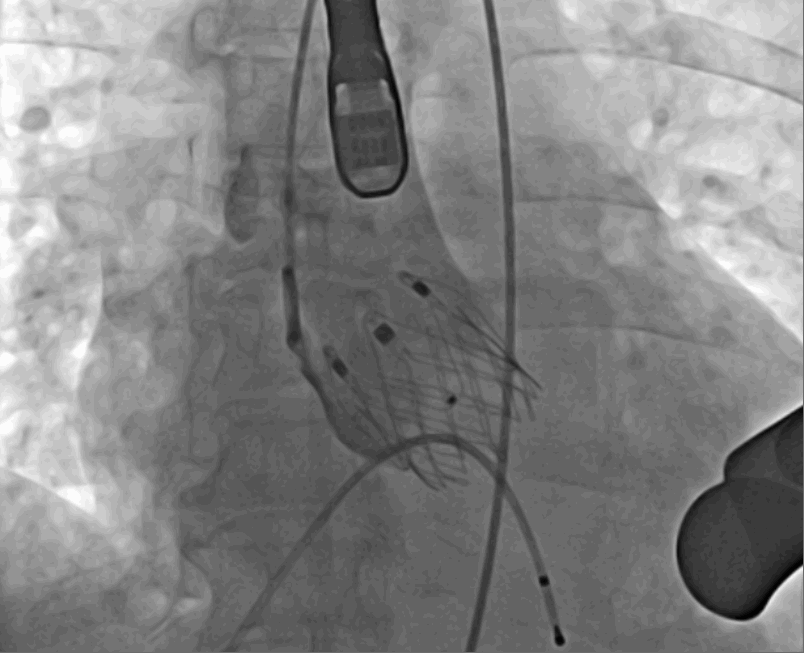

術(shù)前DSA影像圖

術(shù)中釋放定位鍵后DSA影像圖

術(shù)中瓣膜釋放過程